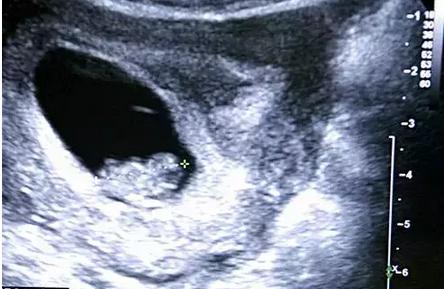

说法8: 胎囊形状看男女

一般情况下,在孕早期,怀孕5周以后,B超可看见小胎囊,胎囊约占宫腔不到1/4,或可见胎芽。如果是正常的宫内妊娠,怀孕40天左右可以通过B超在子宫内看到孕囊。

孕囊大小看胎儿性别:有传言说,如果孕囊大小的长和宽的相差在一倍以上,那么男宝宝可能性大。长和宽相等,或者相差不大的话,很可能是个女宝宝。有妈妈回顾起当年怀孕时的B超数据,来验证了一下,比如有位妈妈在怀孕8周时,孕囊大小是16mm×17mm,结果生下了一位小公主。

孕囊形状看胎儿性别:有人认为,孕囊形状可以看出胎儿是男是女。一般说来,如果孕囊的形状像茄子,或者是呈长条状的,则怀上男宝宝的可能性大;而如果孕囊是椭圆形或圆形的,那么很可能就是个女宝宝了。